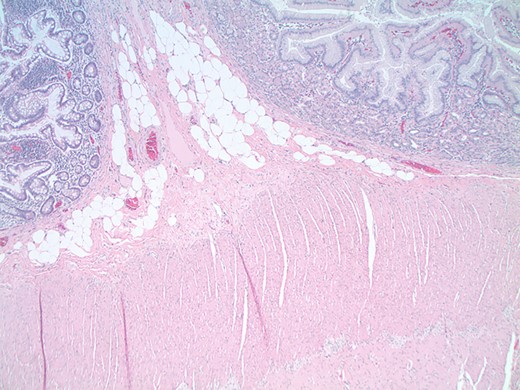

A 26-year-old woman with a history of omphalocele status post repair as a neonate presented to the emergency department (ED) for evaluation of recurrent severe abdominal pain. The abdominal pain was crampy, burning, periumbilical and associated with anorexia, bloating and constipation, mildly improved with induced vomiting. The patient experienced similar symptoms 1 year prior and underwent upper and lower endoscopy, gastric emptying study, and an abdominal ultrasound, all unremarkable. On presentation to the ED, her vital signs and laboratory results were all within normal limits. Conventional CT scan and CT enterography demonstrated a focally dilated segment of small bowel with normal afferent and efferent bowel on either side. Although imaging revealed no evidence of bowel obstruction or mass, diagnostic laparoscopy was performed due to her persistent symptoms. At laparoscopy, a 20 cm segment of abnormally dilated small bowel was identified in the mid ileum with a maximum width of 7 cm, bordered by normal-caliber small bowel (Fig. 1). The dilated segment was resected and an ileo-ileal anastomosis was performed. The resected segment was found to contain a 7 × 4.5 cm2 discrete island of abnormal appearing mucosa with rugal folding (Fig. 2). Histology revealed that this area consisted of heterotopic gastric glandular and foveolar epithelium with no abnormalities identified within the neuronal plexus proximal or distal to this mass (Figs 3 and 4). The patient had an uneventful recovery and was discharged home on postoperative day three. At 6-month follow-up, she reported no recurrence of her symptoms.

Low-power magnification (×40) views of the interface between the gastric heterotopia (right) and the small intestinal epithelium (left). Note that the muscularis propria (bottom) contains an intact neuronal plexus between the muscular layers.